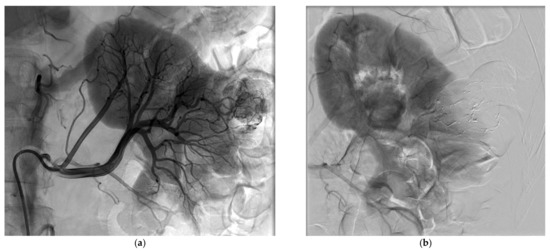

Table 4 reports the features of the PCA procedures. Complete ablation was obtained for all patients and no immediate complications were visible on the control unenhanced CT-scan performed at the end of the procedure. Five patients required hydrodissection prior to ablation. No patient reported more than moderate pain after PCA. No ice-ball cracking occurred. Figure 3 and Figure 4 show examples of PCA of renal cell carcinoma after SAE.

Figure 3.

CT-guided percutaneous cryoablation procedure of a renal cell carcinoma of the left kidney performed after selective arterial embolization using NBCA/Lipiodol® mixture. (a) Enhanced CT-scan for trajectory planification showing a complete devascularization of the tumor. Note the Lipiodol® uptake in the tumor area that can increase targeting accuracy. (b) Volume rendering reconstruction showing the cryoprobes placement. (c) Unenhanced control CT-scan post-ablation showing the optimal coverage of the tumor without any immediate complication.